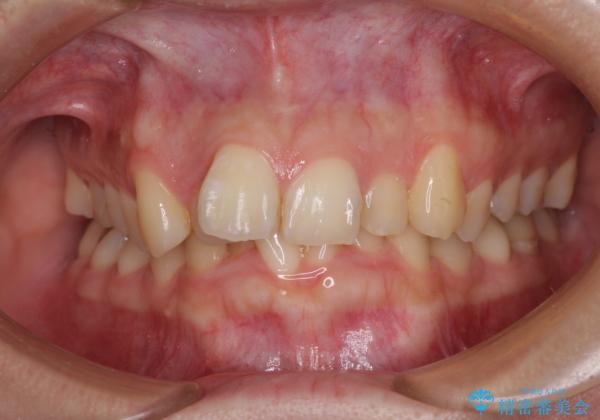

- 前歯のデコボコを気にして来院された患者様です。

上下の前歯にデコボコがあり、更にはディープバイトにより下顎前歯の大半が隠れている状態でした。

上顎左右第一小臼歯の2本を抜歯し、ワイヤー装置を使用して咬み合わせ高さを改善しながら、歯列を整えて行くこととしました。